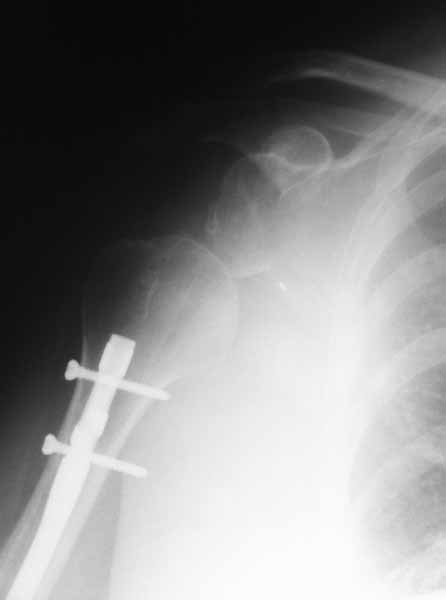

После БИОС

[ Ответить ]